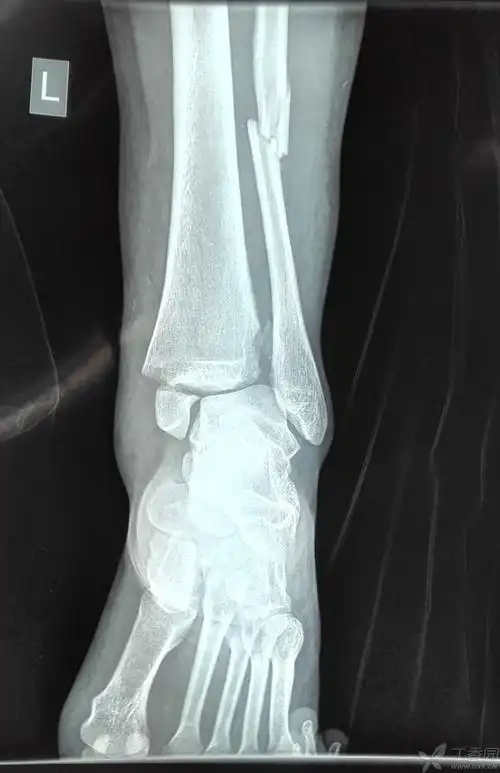

典型踝关节骨折的治疗讨论

脚踝左腓骨远端骨折月记

踝关节骨折l-h旋后外旋4度损伤病例分享 - 好大夫在线

甘肃省人民医院骨一科杨青山副主任医师团队:踝关节骨折

踝关节骨折治疗选择

右脚踝扭伤,腓骨骨折,关节移位.请看x光片,谢谢.